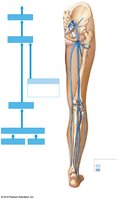

Arterial Supply to the Lower Limb

The abdominal aorta divides into the right and left common iliac arteries, which further branch to supply the pelvis and lower limbs (internal and external iliac, femoral, popliteal, tibial arteries).

Venous Return from the Lower Limb

Blood from the lower limb is returned via the plantar and dorsal venous arches, which drain into the anterior and posterior tibial veins, popliteal vein, femoral vein, and ultimately the external and common iliac veins. The great and small saphenous veins are major superficial veins of the lower limb.